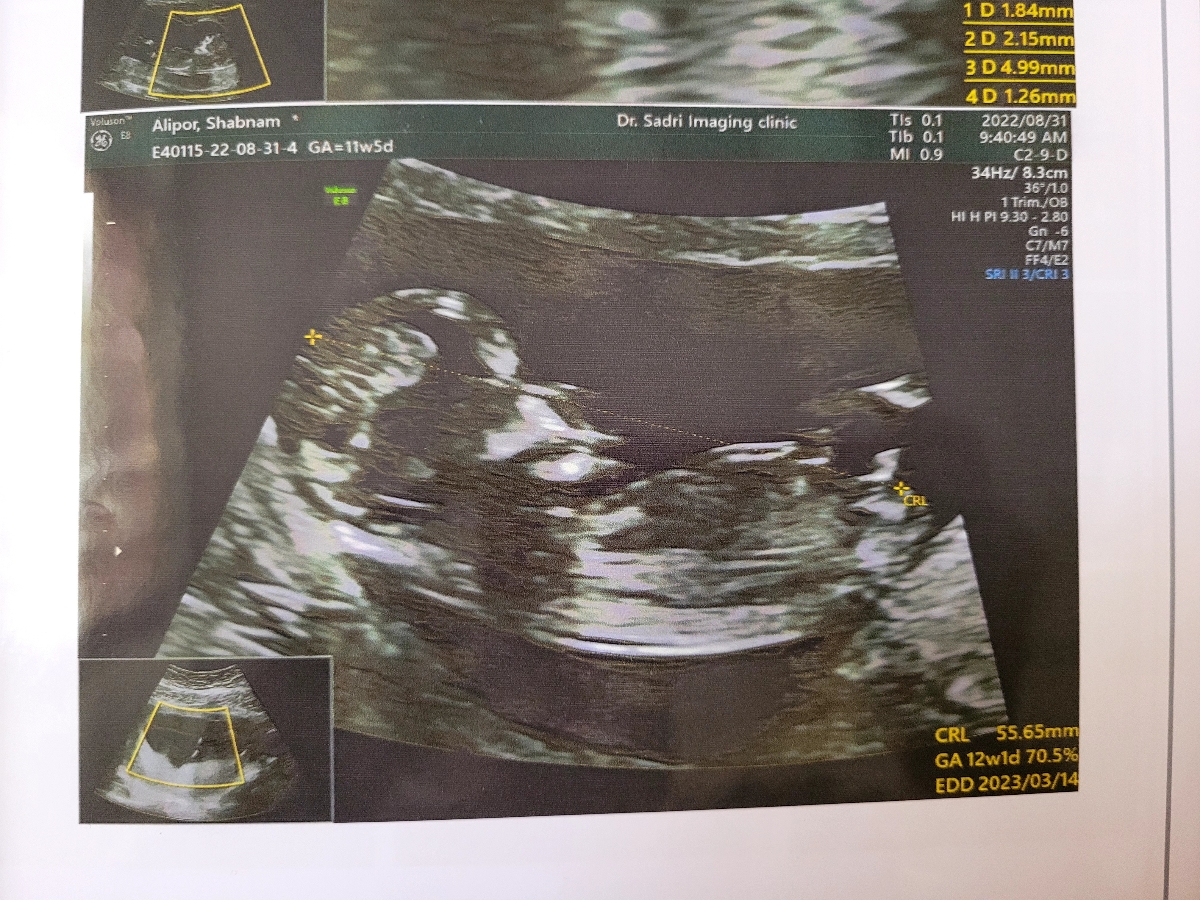

خانما من سونو گرافی ntدادم بنظرتون جنسیتش چیه خیلی ذوق دارم زود بفهمم

عکس سونوتو اگ داری بفرس

پسر

پسره احتمال زیاد

پسرررره

پسره

سرش مثل برا من مربعی هست

دکتر سونو کردنی با اطمینان کامل نمیگه

حدس میزنن فقط